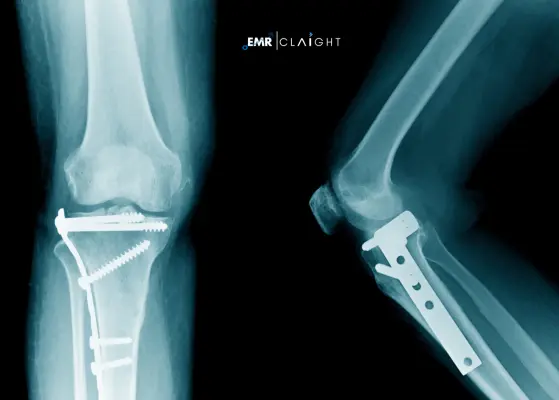

Fracture fixation products are medical devices used to stabilize broken bones so that proper alignment and healing can occur. The common products are plates, screws, nails, rods, and external fixators. They play a very important role in orthopedics as they help treat fractures and ensure the stability of the bones.

The market is growing due to an aging population, rising road accident incidence, and growing awareness about high-end orthopedic care. Technological advancements like the use of bioresorbable materials and robotic surgeries have increased demand for these products in hospitals and clinics.